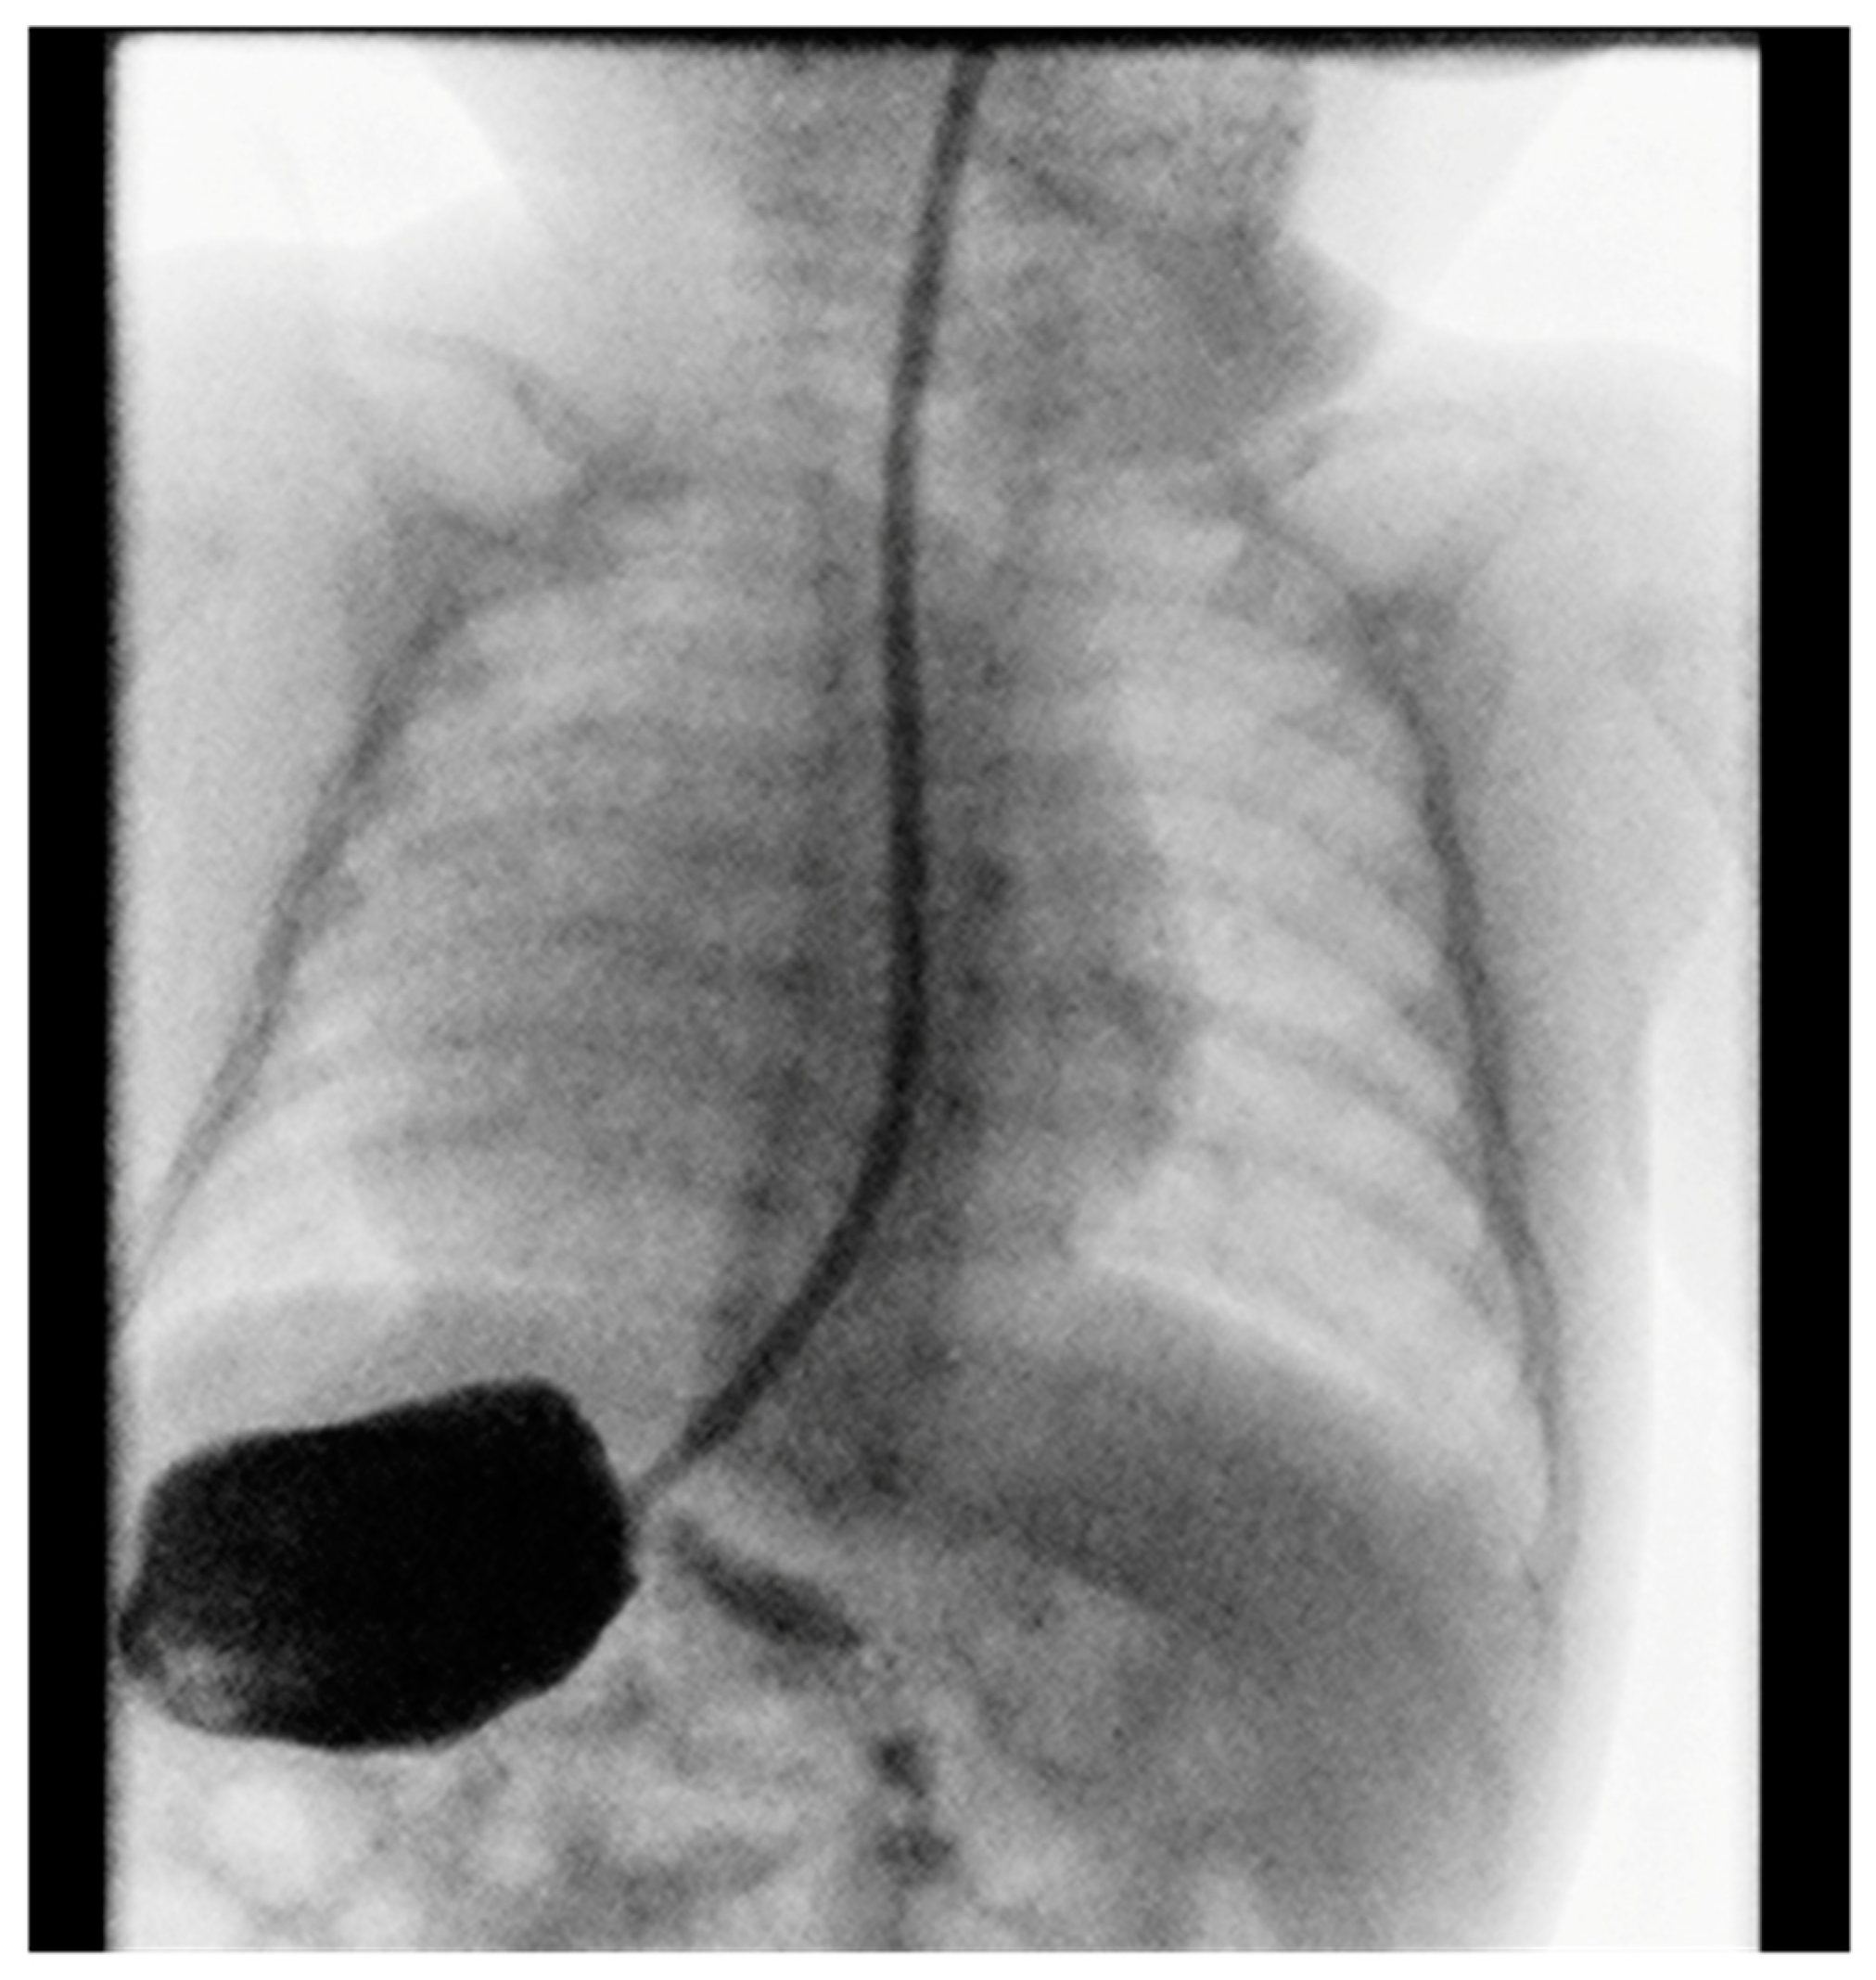

Contrast imaging of the esophagus and stomach shows a normal presentation of the esophagus with the stomach positioned on the right (Figure 2).

Gastroduodenal radiography with contrast showed stomach in the right hemiabdomen. Stomach and duodenum had normal structure and motility. There were no signs of hiatus hernia or gastroesophageal reflux, and there were no obstructions to the passage of contrast fluid.

Figure 2. Position of the stomach on the right.